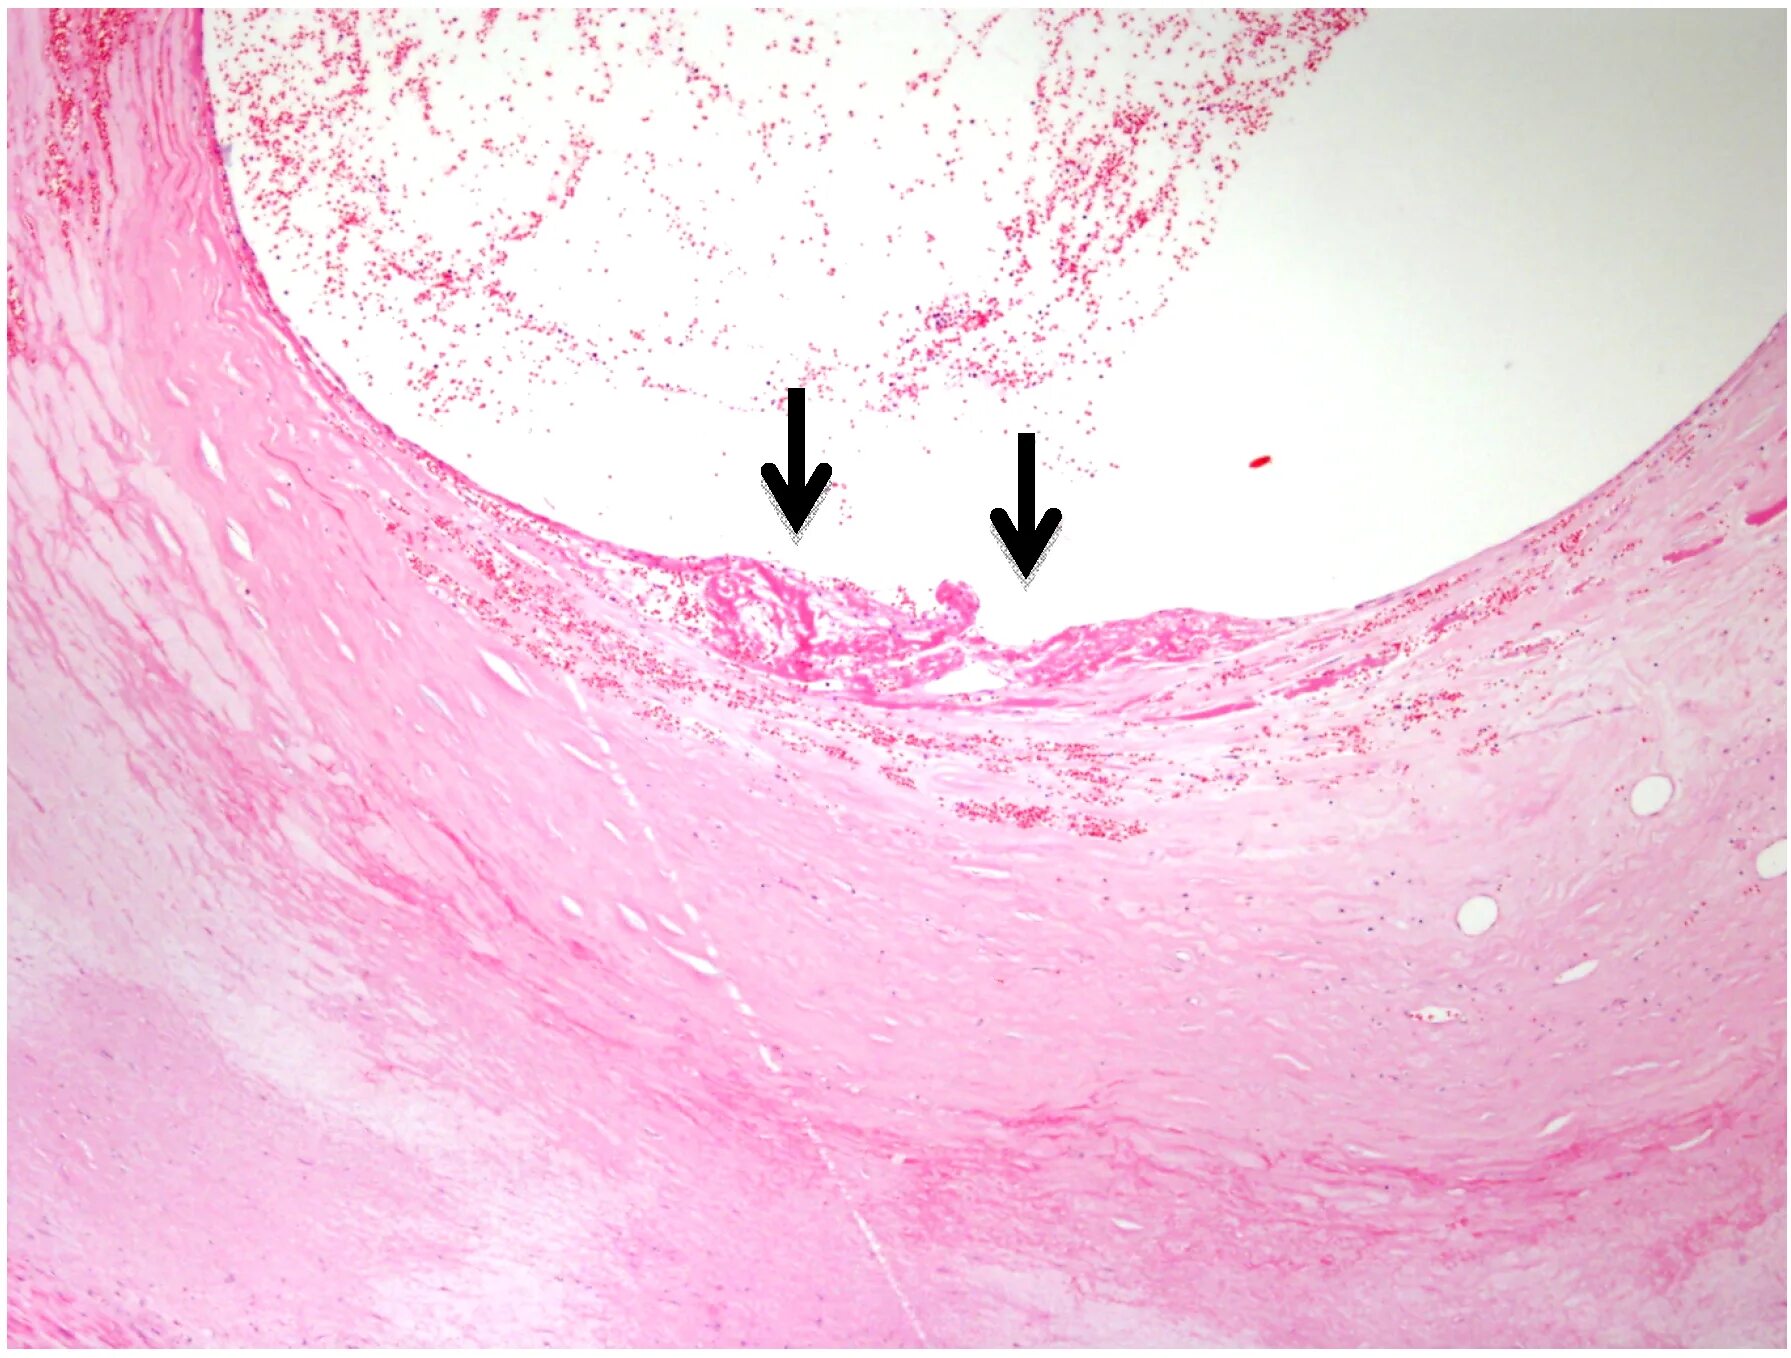

Атеросклероз аорты препарат